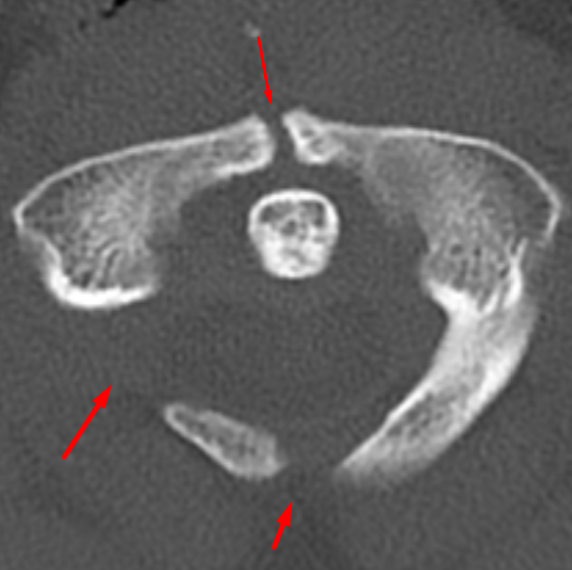

Age: 14

Sex: Male

Indication: Trauma